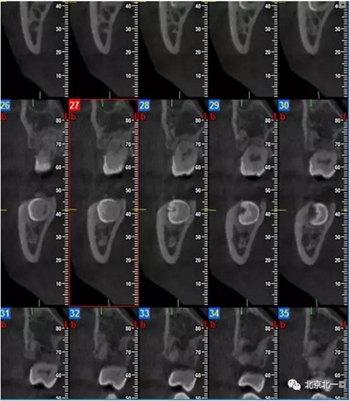

CBCT:骨量高度及寬度可, 48埋伏,低位阻生.37近中骨吸收

診斷:下頜牙列缺損, 48低位埋伏阻生 37 牙周炎

治療計劃:46種植, 同期拔除48 正畸扶正47.